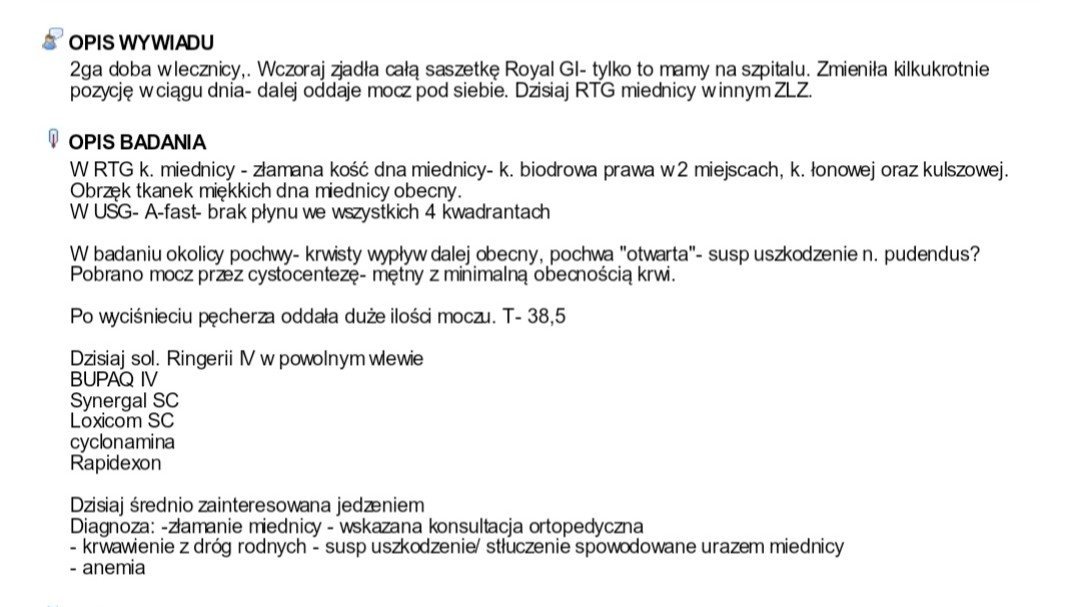

To kocie nieszczęście trafiło do nas 2 stycznia. Kotka od razu trafiła do lecznicy, otrzymała leki, a już kolejnego dnia przyjął ją szpital. Krwawienie z dróg rodnych, niska temperatura, połamana miednica. Trwa walka o jej życie, niedługo będziemy ją konsultować z ortopedą.